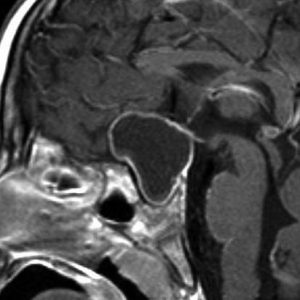

成人の第3脳室内部に局在する頭蓋咽頭腫です。経脳梁法で両側のモンロー孔から全摘出しました。下垂体組織は残っています。これは乳頭状頭蓋咽頭腫と呼ばれるもので,成人にしか発生しません,のう胞がなく石灰化もないのが大きな特徴です。境界が明瞭で柔らかく摘出が簡単なタイプとして知られています。この患者さんも術後に下垂体機能不全も視床下部障害も生じませんでした。